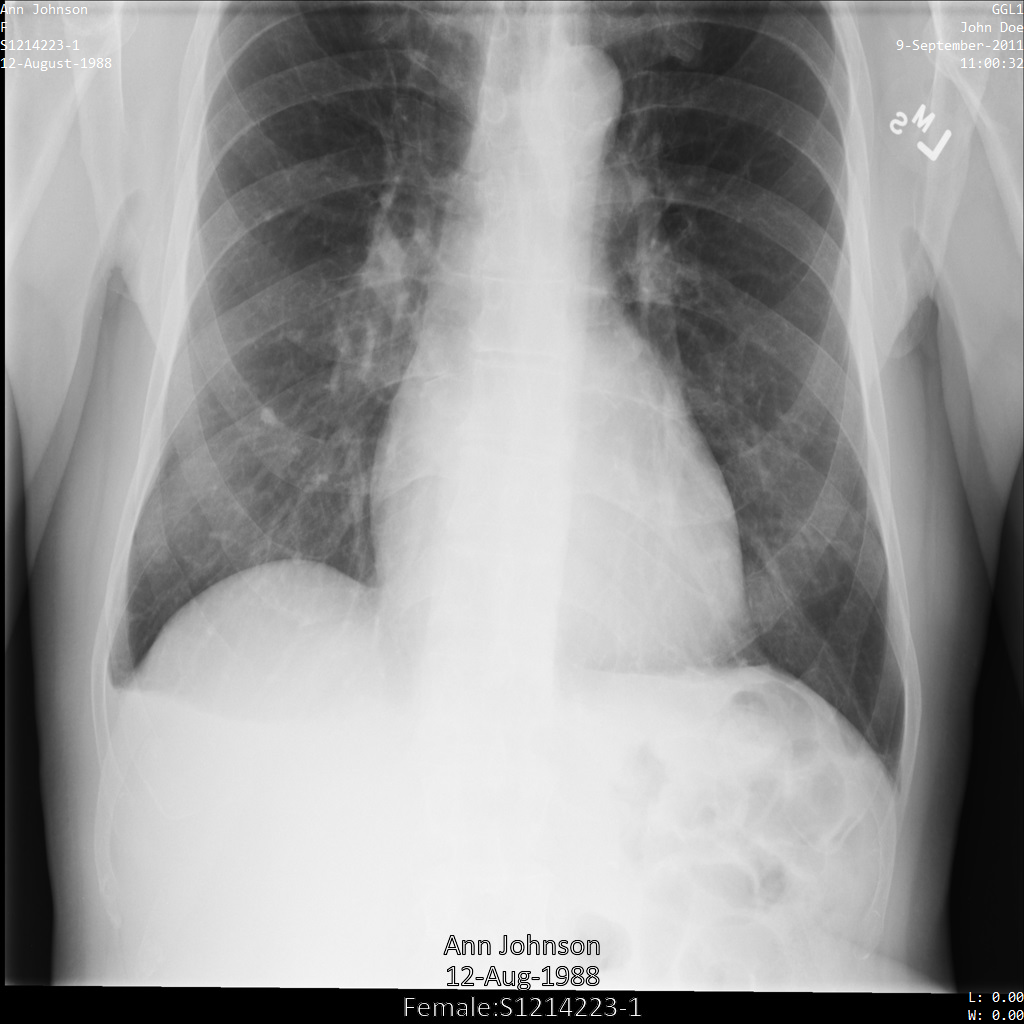

Depois de remover a identificação da imagem com REDACT_SENSITIVE_TEXT_CLEAN_DESCRIPTORS

, a imagem

tem o seguinte aspeto. Repare que nem todo o texto incorporado na parte inferior da imagem foi ocultado. O texto Female

continua a ser apresentado porque PatientSex (0010,0040)

não é um dos infoTypes DICOM predefinidos.

REDACT_SENSITIVE_TEXT_CLEAN_DESCRIPTORS